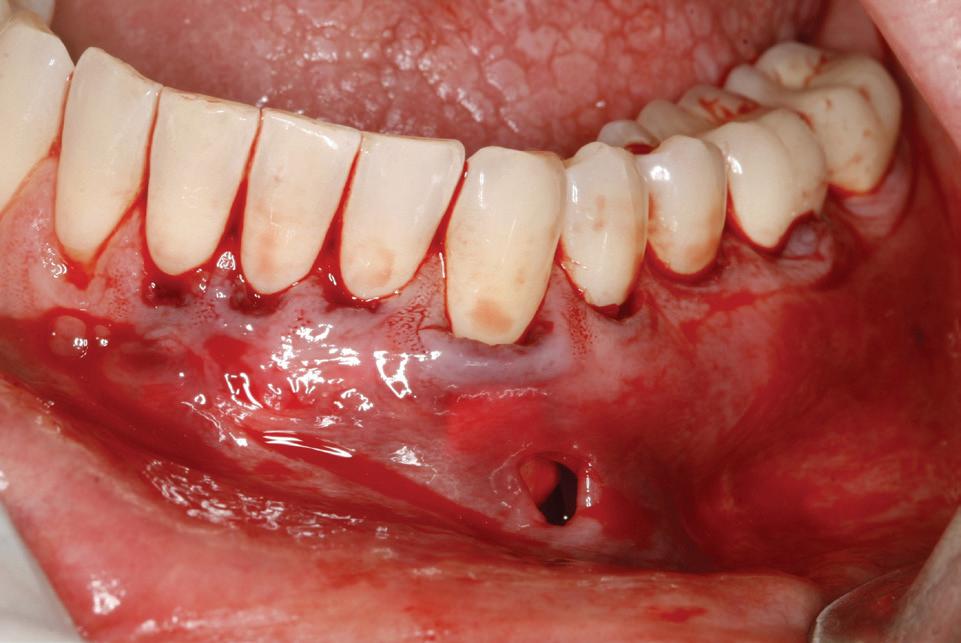

• Similar altor tehnici din stomatologie, procedurile utilizate pentru augmentarea țesuturilor moi ale rădăcinilor denudate au evoluat de-a lungul anilor. Accentul se pune astăzi pe cele minim invazive, parodontologii depunând eforturi pentru o predictibilitate mai mare, cu morbiditate locală scăzută. Regăsiți descrisă tehnica smile (labială sulculară internă modificată) cu tunelizare combinată cu xenogrefă și PRF, care necesită semnificativ mai puține instrumente decât alte proceduri comparabile.

Colaborarea profesională și planificarea ghidată protetic sunt esențiale pentru rezultate predictibile de succes.